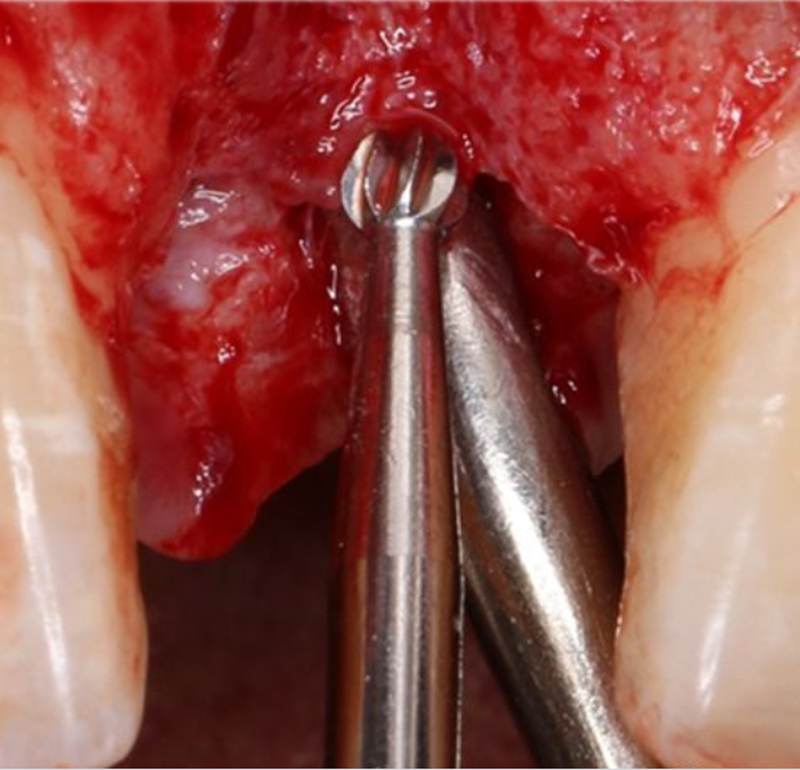

逐級擴孔

2.2mm 先鋒鉆確定植入深度及軸向

在實時導(dǎo)航系統(tǒng)中,實時引導(dǎo)先鋒鉆按照術(shù)前設(shè)計種植體軸向及深度進行擴孔

2.8mm 擴孔鉆按種植體軸向擴大窩洞

在實時導(dǎo)航系統(tǒng)中,實時引導(dǎo)擴孔鉆按照術(shù)前設(shè)計種植體軸向及深度進行擴孔